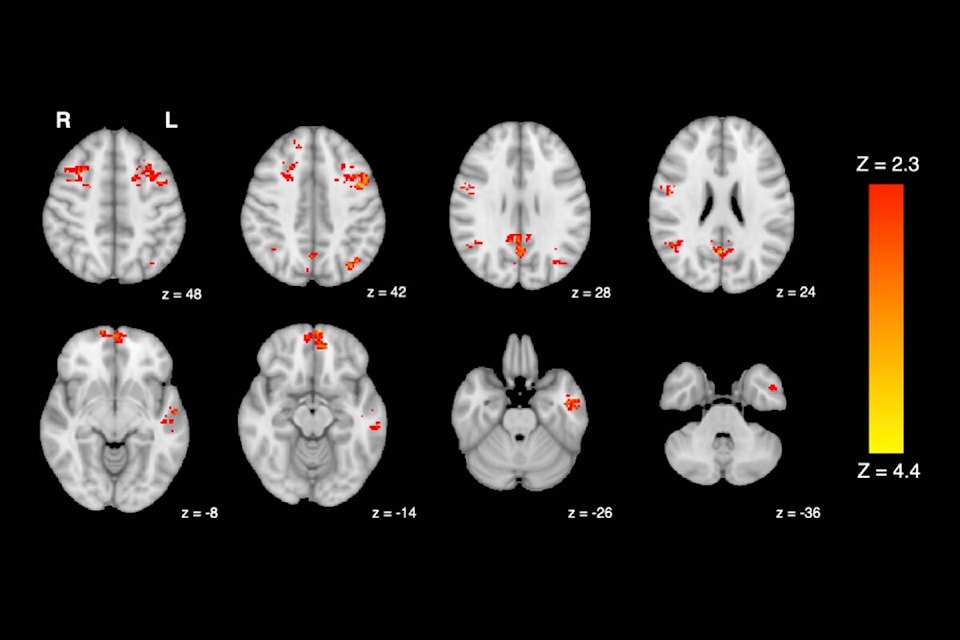

It also found that just two hours of exposure to diesel exhaust causes a decrease in the brain’s functional connectivity, which reflects the ability of different areas of the brain to interact and communicate with one another.

Researchers analyzed changes in the brain’s default mode network (DMN), a set of inter-connected brain regions that play a significant role in memory and internal thought. The fMRIs revealed that participants had decreased functional connectivity in widespread regions of the DMN after exposure to diesel exhaust, compared to filtered air.

“We know that altered functional connectivity in the DMN has been associated with reduced cognitive performance and symptoms of depression, so it’s concerning to see traffic pollution interrupting these same networks,” Jodie Gawryluk, assistant professor of psychology at UVic, told Black Press Media. “But more studies are needed to look at the long-term effects, like what happens after we have repeated exposures for a long time – we might not be able to recover so easily from that.”